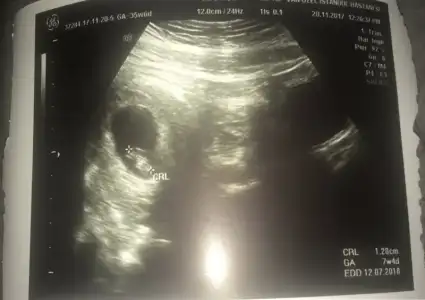

Canim benim oglum sagdaydi :) simdi gene sagda :) birde su var kese yuvarlaksa kiz fasulye gibiyse sekli erkek mis benim oglusumda fasulye gibiydi simdi yusyuvarlak acaba ne :) once saglik tabi ama insan icindeki minigin ne oldugunu merak ediyor

Canım ama bu kesenin sağ da veya solda olması değil kesenin içindeki bebeğin sağ ya da solda olması mesela kese sağ da bebek kesenin içinde sol taraftaysa erkek yazıyor

Bu arada Allahım bağışlasın evlatlarını canım. Bide benim ikisinde de ayrı ultrason resmi ekledim biri fasulye :) çarşamba nasıl olacak bakalım çok heycanlıyım

Eklentiler

• 0D36B26E-F23E-47E7-B70F-327633403338.webp

0D36B26E-F23E-47E7-B70F-327633403338.webp

18 KB · Görüntüleme: 88

• F8604ACB-9F5D-455D-AFAA-175391BB23B8.webp

F8604ACB-9F5D-455D-AFAA-175391BB23B8.webp

19,3 KB · Görüntüleme: 84